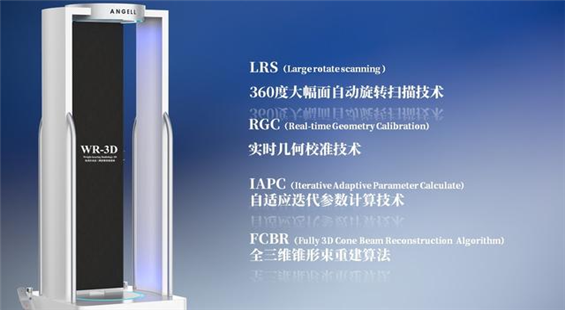

在DR设备的选择上,当地政府相关部门与卡若区人民医院基于医院的临床科室需求,定位于采购多功能的动态数字化X线设备,减少医疗资源的浪费,提升设备配置的效率。经过前期的详细设备功能与图像考察,在公开、公平、公正的招标遴选程序下,亿万28入口网页版-亿万28网页在线玩-万28官网下载最新版-亿万e网址pg-亿万28pg电子-亿万28赏金女王-亿万28娱乐科技动态多功能诊断专用DR—腾灵进入昌都卡若区人民医院,开启了其服务藏区百姓的健康使命。

图4:腾灵——动态多功能诊断专用DR

作为一款动态多功能诊断专用DR设备,腾灵支持高清摄片、透视摄影、造影摄影、全脊柱摄影、全下肢摄影检查于一身,满足低人口密度地区的多种数字化X线摄影检查需求。在卡若区人民医院,每天大约有60人左右的检查人次,来自于一区十县 24个镇118乡的藏区百姓,腾灵在过去近一年的服役中赢得了放射科主任及主管技师的一致认可。